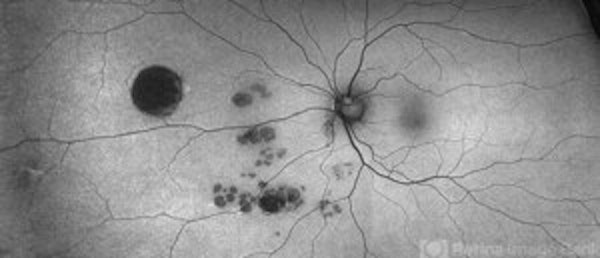

Right eye fundus photograph of a 42 year old asymptomatic male demonstrating a superotemporal solitary large Congenital Hypertrophy of Retinal Pigment Epithelium (CHRPE) lesion.